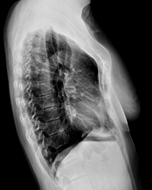

흉부 X선 검사로 가슴을 옆으로 찍어보면 흉골 즉 앞가슴의 모양을 알 수 있다. 더 자세한 건 흉부 컴퓨터단층촬영(CT)을 해봐야 하지만 흉부 X선 측면 검사와 진찰만으로 오목가슴·새가슴·늑연골 돌출을 구분할 수 있다.

오목가슴(그림 1. B)이면 흉골이 함몰되면서 폐·심장을 동시에 누르지만 폐 기능은 거의 정상이다. 하지만 심장 기능은 좀 달라진다. 안정 시에는 문제없지만 운동하거나 힘든 일할 때 심장박동이 빨라지면 심장 박출량이 충분하지 않아 빨리 지치고 지구력이 떨어진다.

전반적으로 전흉벽이 납작하거나, 부분적으로 심하게 함몰됐거나, 비대칭으로 함몰됐거나, 특히 왼쪽으로 비대칭 함몰이라면 심장이 크게 눌리기 마련이므로 조기에 수술로 교정하는 게 좋다.

새가슴(그림 1. C)이라면 심장·폐가 눌리지 않기에 치료하지 않아도 될 때도 있다. 하지만 새가슴인 어린이는 여름철에 얇은 옷을 입으면 너무 티가 나기에 스트레스를 많이 받게 된다. 수영장이나 대중목욕탕 등 웃옷을 벗었을 때 친구들에게서 지적을 받기에 민감해질 수밖에 없다.

전반적으로 볼록하거나, 상부 새가슴, 하부 새가슴, 부분 돌출 새가슴, 비대칭 새가슴일 때, 특히 상부 및 부분 돌출 새가슴이라면 조기에 치료해야 한다. 이 중 상부 새가슴이라면 아래는 정상이지만 상대적으로 오목해 보인다(그림 2). 흉부압박보조기로 대부분 치료된다.